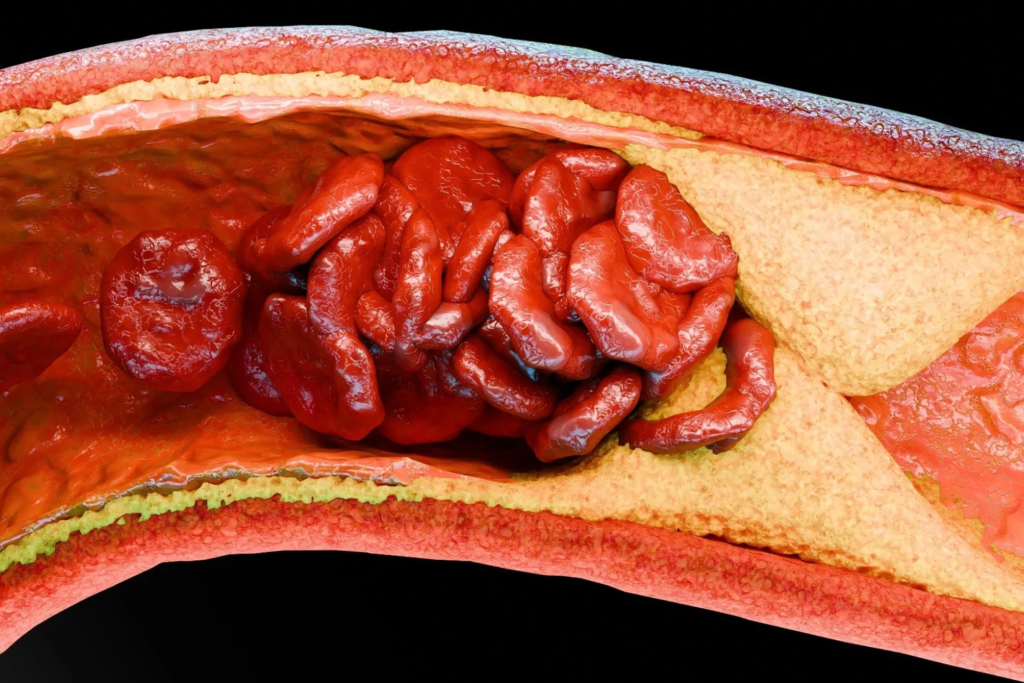

Peritonealne metastaze (PM) karcinoma želuca ostaju jedan od najtežih terapijskih problema, jer medijana preživljavanja uz standardnu sistemsku hemioterapiju retko prelazi 11 meseci, a peritoneum je i dalje najčešće mesto neuspeha lečenja. U teoriji, intraperitonealna (IP) primena paklitaksela zaobilazi ovaj problem jer omogućava postizavanje visoke lokalne koncentracije leka uz ograničenu sistemsku ekspoziciju. Ipak, do sada nijedna randomizovana studija faze 3 nije potvrdila prednost ovog pristupa u OS.